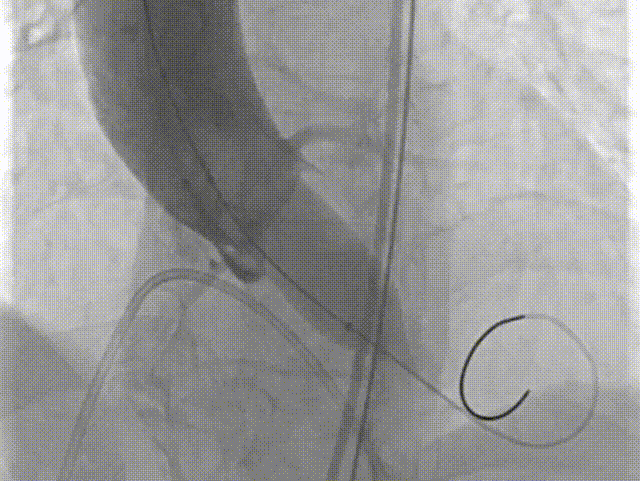

手术过程

主动脉根部造影

18球囊预扩张

瓣膜定位

瓣膜释放过程

瓣膜形态

18球囊后扩张

瓣膜最终形态